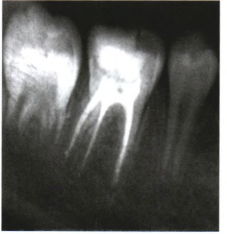

【辅助检查】

临床检查可见右下第一恒磨牙远中牙合面深大龋洞(见图1),可探及露髓孔,叩痛(±),患牙无松动,牙龈无异常,牙髓冷测试敏感。根尖x线片示根尖孔闭合,根尖周未见低密度影及根周膜增宽,未见根尖弯曲。

6个月复查时患者无不适,此时根尖x线片仍未观察到牙根的异常弯曲及穿孔,同时根尖周未见低密度影。